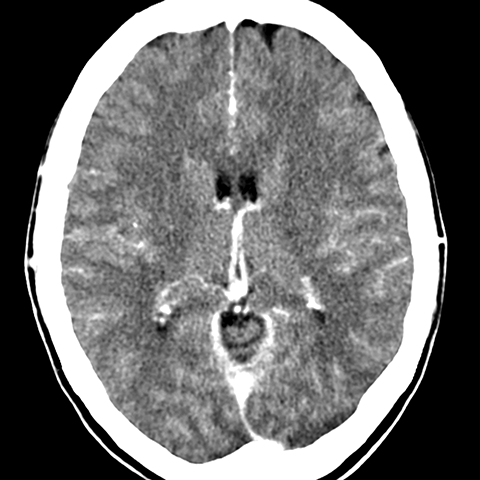

Cerebral Hemispheres, CT (normal) [5 of 6]